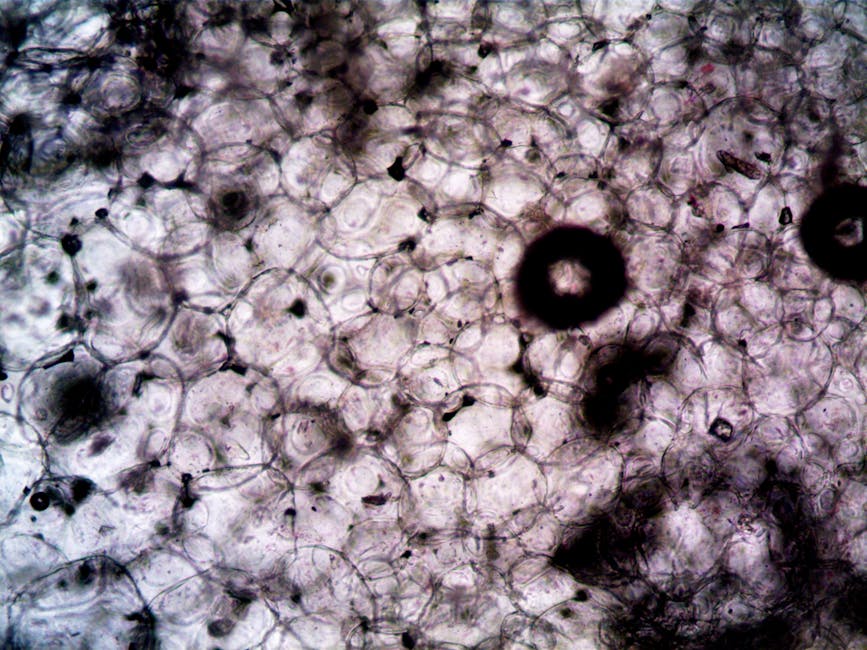

The study, which was conducted by a team of researchers from a leading university, used a combination of genetic and biochemical approaches to identify a specific gene that is involved in the regeneration of human tissues. The gene, which is known as REG1, was found to play a critical role in the activation of stem cells and the promotion of tissue repair. The researchers used a variety of experimental models, including cell cultures and animal models, to study the function of the REG1 gene and its role in regeneration. Their findings showed that the gene is essential for the regeneration of multiple tissue types, including skin, muscle, and nerve tissue.